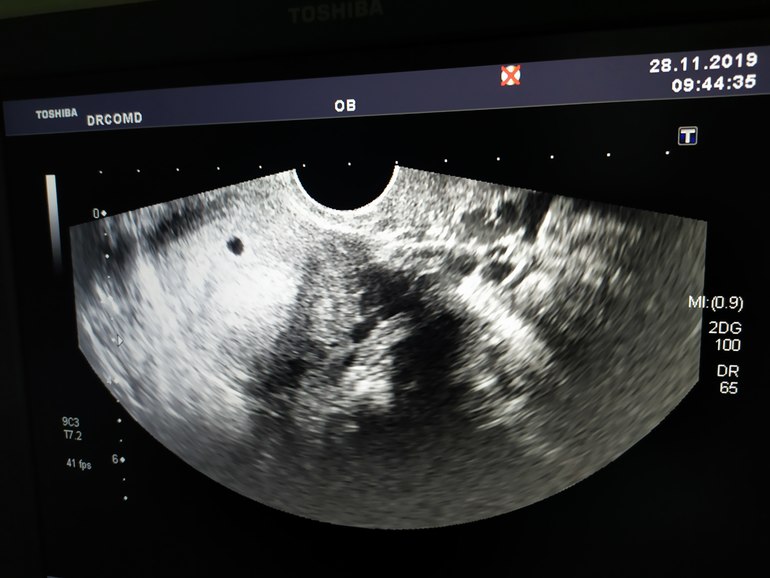

Наше 1 УЗИ

Сегодня была на УЗИ. Акушерская 5н 1д.

ПЯ в матке, 5мм, желточный мешочек 1 мм. Контроль через неделю